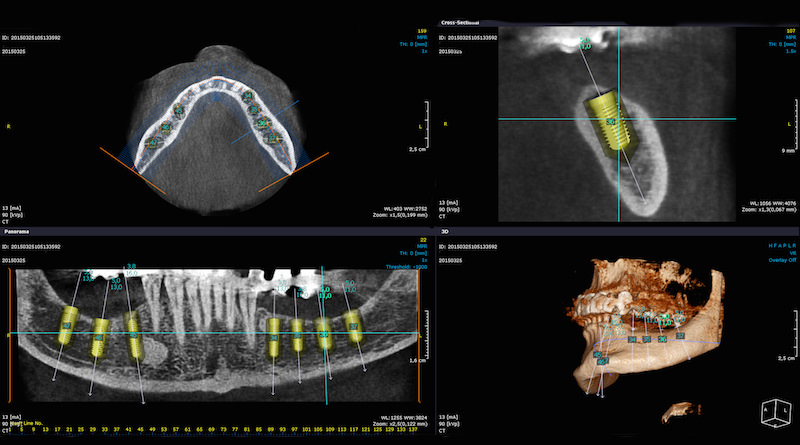

DSD – Digital Smile Design è la base di pianificazione delle fasi di lavoro.